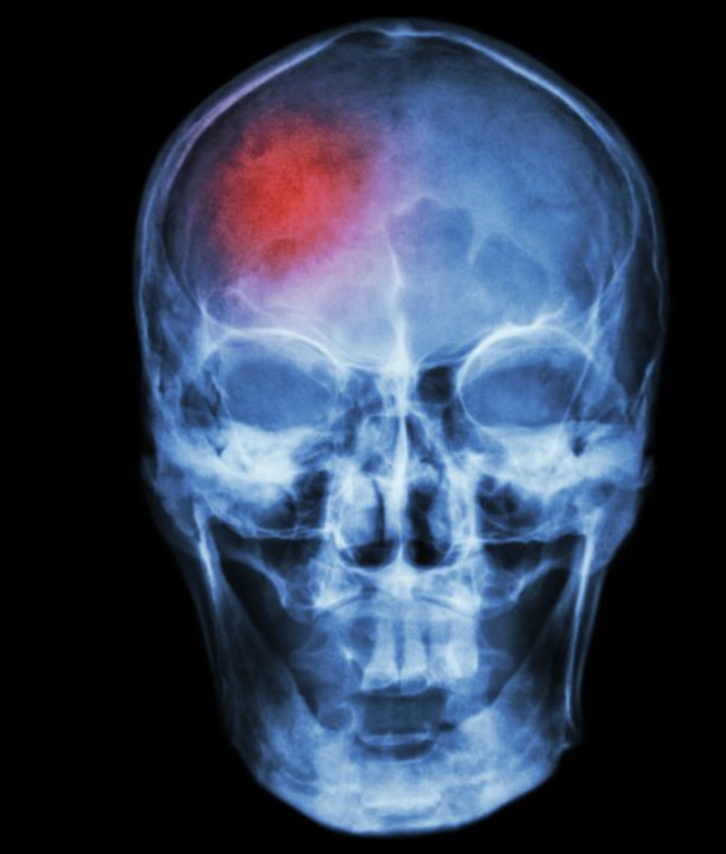

Concussion symptoms that linger after a car accident can be frustrating and confusing for Kansas City residents. Many expect rest to be enough, only to find that headaches, dizziness, or vision problems persist. The truth is, successful concussion rehabilitation depends on a thorough evaluation of three interconnected systems: the neck, the balance system, and the eyes.

tbi after a car accident kansas city